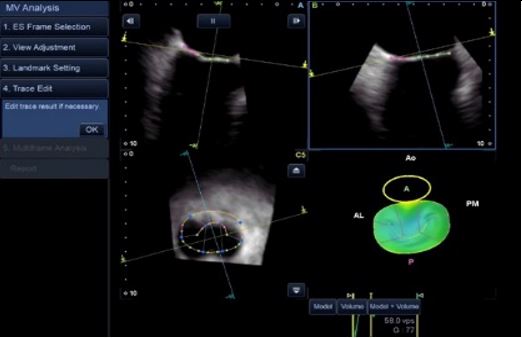

Аналіз мітрального клапана в 4D (4D MVA)

Цей унікальний інструмент забезпечує анатомічну та функціональну оцінку мітрального клапана, проводячи близько 40 вимірювань за 30 секунд, та допомогає лікарю при плануванні інтервенційного втручання, наприклад для операції транскатетерної імплантації мітрального клапана.

- Функціональна оцінка мітрального клапана

- 4-віконний дисплей (обрані користувачем зрізи, різні площини сканування, 3D-реконструкція)

- Автоматизовані вимірювання мітрального клапана з виведенням в реальному часі більш ніж 40 показників

- Реконструкція мітрального клапана візуалізує форму стулок клапана, що допомагає оцінити пролапс або деформацію.